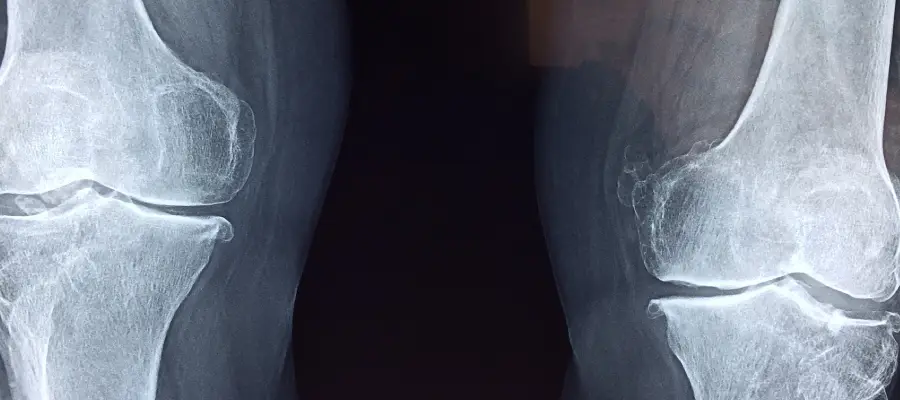

Günümüzde tıbbın gelişmesi ile birlikte, genetik testler akondroplazi tanısında önemli rol oynar. FGFR3 geninde spesifik mutasyonların varlığı, tanıyı neredeyse kesinleştirecek veriler sunar. Bu testler, hem anne karnında hem de doğum sonrası yapılabilmektedir.

Bununla birlikte, röntgen ve MR gibi radyolojik görüntüleme yöntemleri de akondroplazili hastaların kemik yapısını değerlendirmenin önemli araçlarıdır. Özellikle uzun kemiklerin boyu, büyüme plaklarındaki değişimler, kafatası yapısı ve omurga eğrilikleri bu yöntemlerle çok net şekilde analiz edilebilir. Radyolojik bulgular, hem tanı aşamasında hem de tedavi planlaması sırasında yol gösterici niteliktedir.